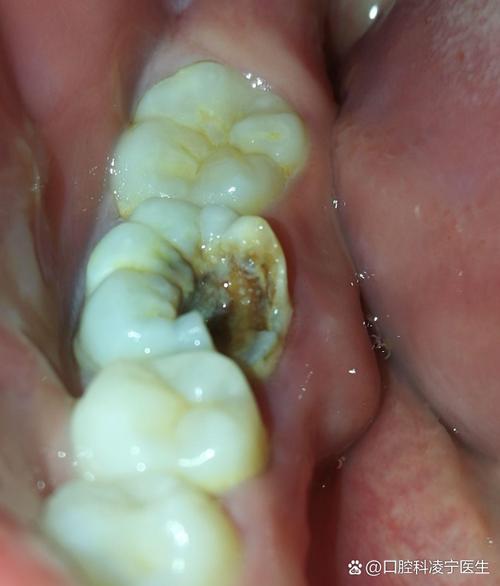

除了矫正过程中的力学因素,其他原因也可能加剧牙根裸露,矫正前若存在未控制的牙周炎(牙龈炎进展到牙周组织感染),会导致牙槽骨 already 吸收,牙龈萎缩,此时矫正可能进一步加重问题;矫正期间口腔卫生维护不当,牙菌斑堆积引发牙龈炎症,长期炎症会破坏牙龈附着;个体差异(如天生牙龈薄、牙根形态异常)和不良习惯(如刷牙用力过猛、咬硬物)也是诱因。

牙根裸露的影响不容忽视,首先是牙齿敏感,患者可能在进食冷饮、甜食或刷牙时感到酸痛,影响生活质量;其次是美观问题,暴露的牙根呈淡黄色,与牙冠颜色差异明显,尤其在前牙区会影响笑容;长期未处理,牙根持续暴露可能导致牙根面龋坏(牙根蛀牙),严重时甚至引发牙齿松动、脱落,威胁口腔健康。